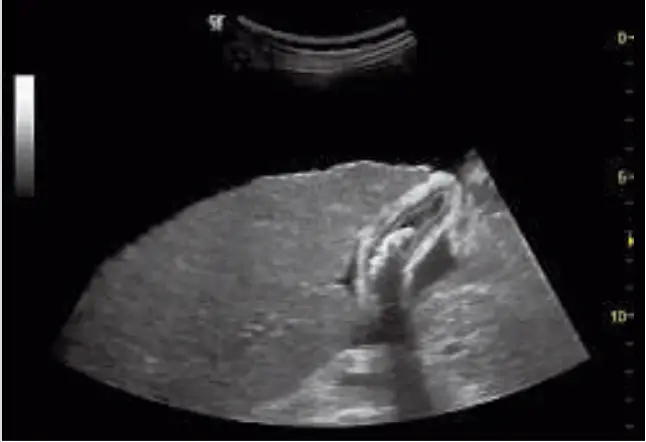

| Ascites, liver, and gallbladder stones are displayed together using the 5CS probe and a combination of Phase Inversion Harmonics and SRI | Neonatal head exam imaging with the 8C probe using CrossXBeam, SRI, and harmonics |

Speckle Reduction Imaging (SRI). Heighten your visibility of organs and lesions with high-definition contrast resolution that suppresses speckle artifacts while maintaining true tissue architecture.

CrossXBeam™. Enhance tissue and border differentiation with real-time spatial compounding acquisition and processing.

Harmonics. Increase resolution and cystic clarity with a combination of coded harmonics and Phase Inversion Harmonics.